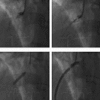

Case report: A 58-year-old sustained chest trauma after a vehicle accident, complicated by acute occlusion of the right coronary artery. Despite invasive intervention the patient deteriorated and died due to multi-organ failure.